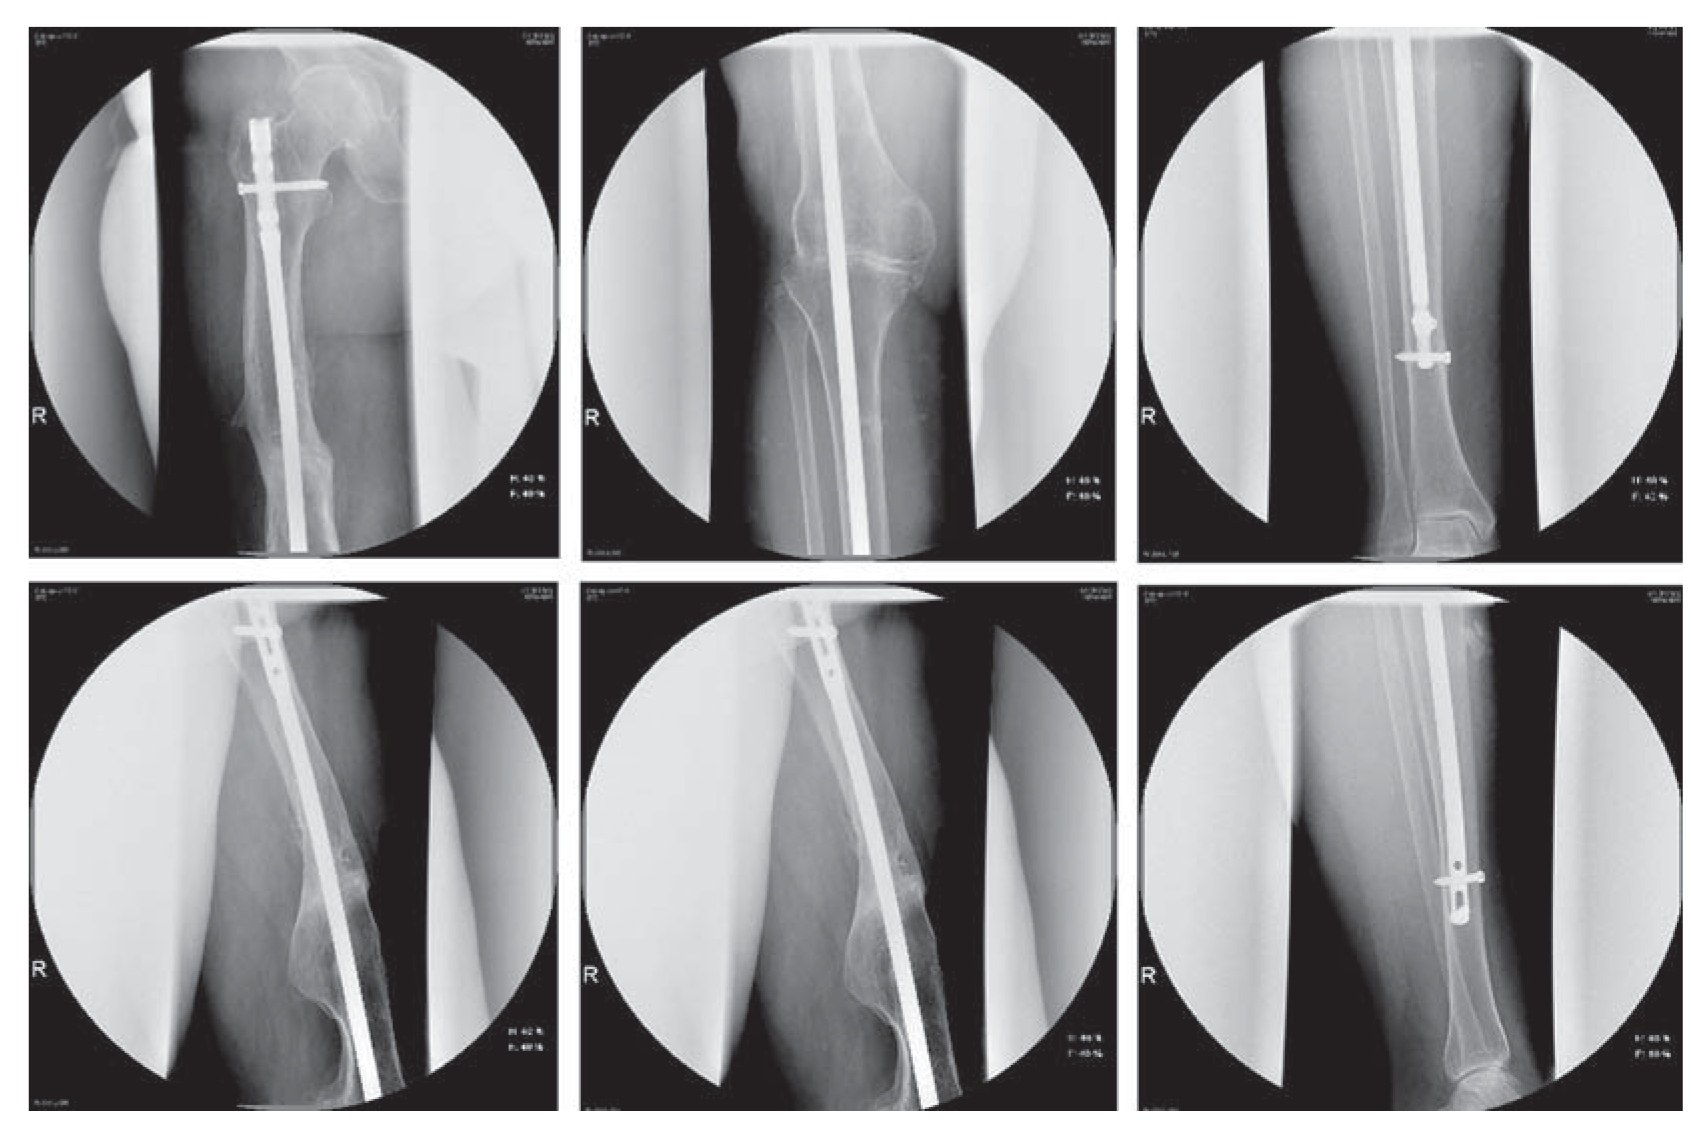

Пациентка А., 56 лет, поступила в клинику ФГБУ «РНИИТО им. Р.Р. Вредена» (далее РНИИТО) 21.04.2017 с диагнозом: консолидированный с варусной и торсионной посттравматической деформацией (перелом диафиза в средней трети) правой бедренной кости посттравматический гонартроз III стадии, болевой синдром, фиброзный анкилоз правого коленного сустава, укорочение правой нижней конечности 5 см (рис. 1). Пациентка была направлена в РНИИТО из региона Российской Федерации для госпитализации с целью получения высокотехнологичной медицинской хирургической помощи.

Рис. 1. Телерентгенограммы обеих нижних конечностей пациентки до операции.

Fig. 1. Long leg films of both lower extremities of the patient before the surgery.

По телерентгенограммам обеих нижних конечностей и рентгенограммам коленного сустава были оценены характер и величина имеющейся деформации правой нижней конечности во фронтальной и сагиттальной плоскостях (23° варусной деформации, 9° антекурвационной деформации). Были зарегистрированы изменения, характерные для посттравматического гонартроза III стадии с преимущественным поражением медиального отдела коленного сустава: значительное сужение суставной щели (по типу «кость на кость»), выраженные костные разрастания по краю мыщелков бедренной и большеберцовой костей, латеральный подвывих голени, признаки пателлофеморального артроза. По данным компьютерной томографии была выявлена наружная торсия бедренной кости 15° на уровне консолидированного с деформацией перелома. По результатам лабораторных исследований признаков системного воспаления у пациентки не было обнаружено.

Рис. 5. Телерентгенограммы пациентки в прямой и боковой проекциях после операции.

Fig. 5. AP and lateral long-leg films of the patient after the surgery.